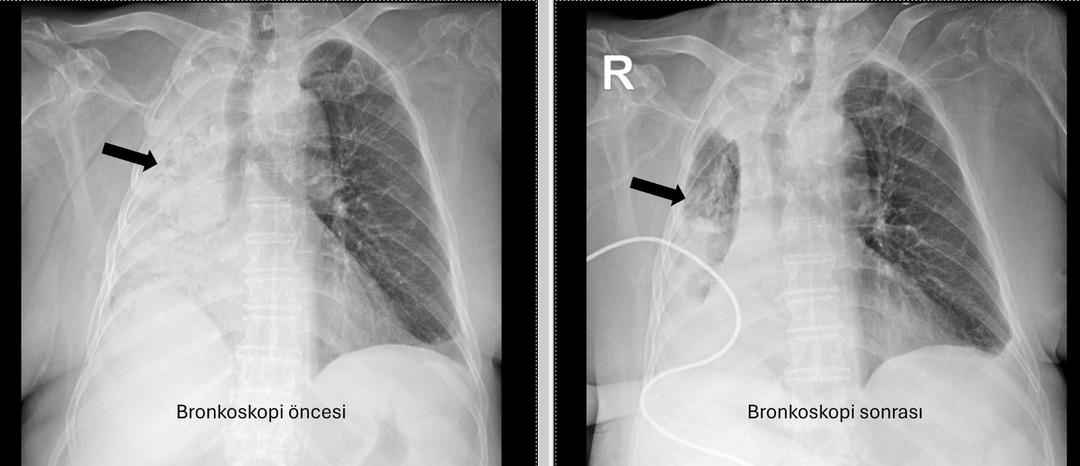

Yediği yemek az kalsın hayatından ediyordu: Sağ akciğeri tamamen kapandı! Soluk borusunu tıkadığı 5 ay sonra ortaya çıktı…

Denizli'de yaşayan 78 yıllık kadın ve emekli bir öğretmen yakın zamanda akciğer enfeksiyonu nedeniyle hastanede idi. 1 ay önce gittiği hastanede bronkoskopinin yapılmasına rağmen, sorunun tespit edilmediği öğrenildi. Yaşlı kadın, sağ akciğerin Pamukkale Üniversite Hastanesi'nin belirlenmesine tamamen kapatıldığı hastaneye gitti.

Pau Ökr Hastaneleri Göğüs Hastalıkları Bölümü. Prof.dr. Üye Dr.Köksel Altōiş Ergur, sağ akciğerler tarafından yapılan sınavlar için tamamen kapatıldı. Acil bronkoskopi planlandı ve prosedür derhal gerçekleştirildi. Dr. Altenishık ergur, hava yollarını incelerken çok yoğun ve karanlık bir salgılama ile esnek bir “bronkoskop” (esnek, katlanabilir), ancak hava yollarının derinlemesine temizlenmesini takiben, bir olaydan dolayı dönüştürüldüğünü ve berrak olduğunu, bir olaydan dolayı dönüştürüldüğünü açıkladığını açıkladığını açıkladığı açıktır. Vücudun açık olduğu açık olduğu açık olduğu açık olduğu açıktı. genel anestezi ile yapılmıştır;

Prof. Alküzek Ergur, hastanın trakeasının nasıl engellendiğini açıkladı: “Havayollarında sıvı emen aspiratörün gücünü kullanarak nesneyi çıkarmak mümkün oldu. Hastanın hastanın tekrar yediği pizzada yediği pizza için daha önemli olduğu öğrenildi.